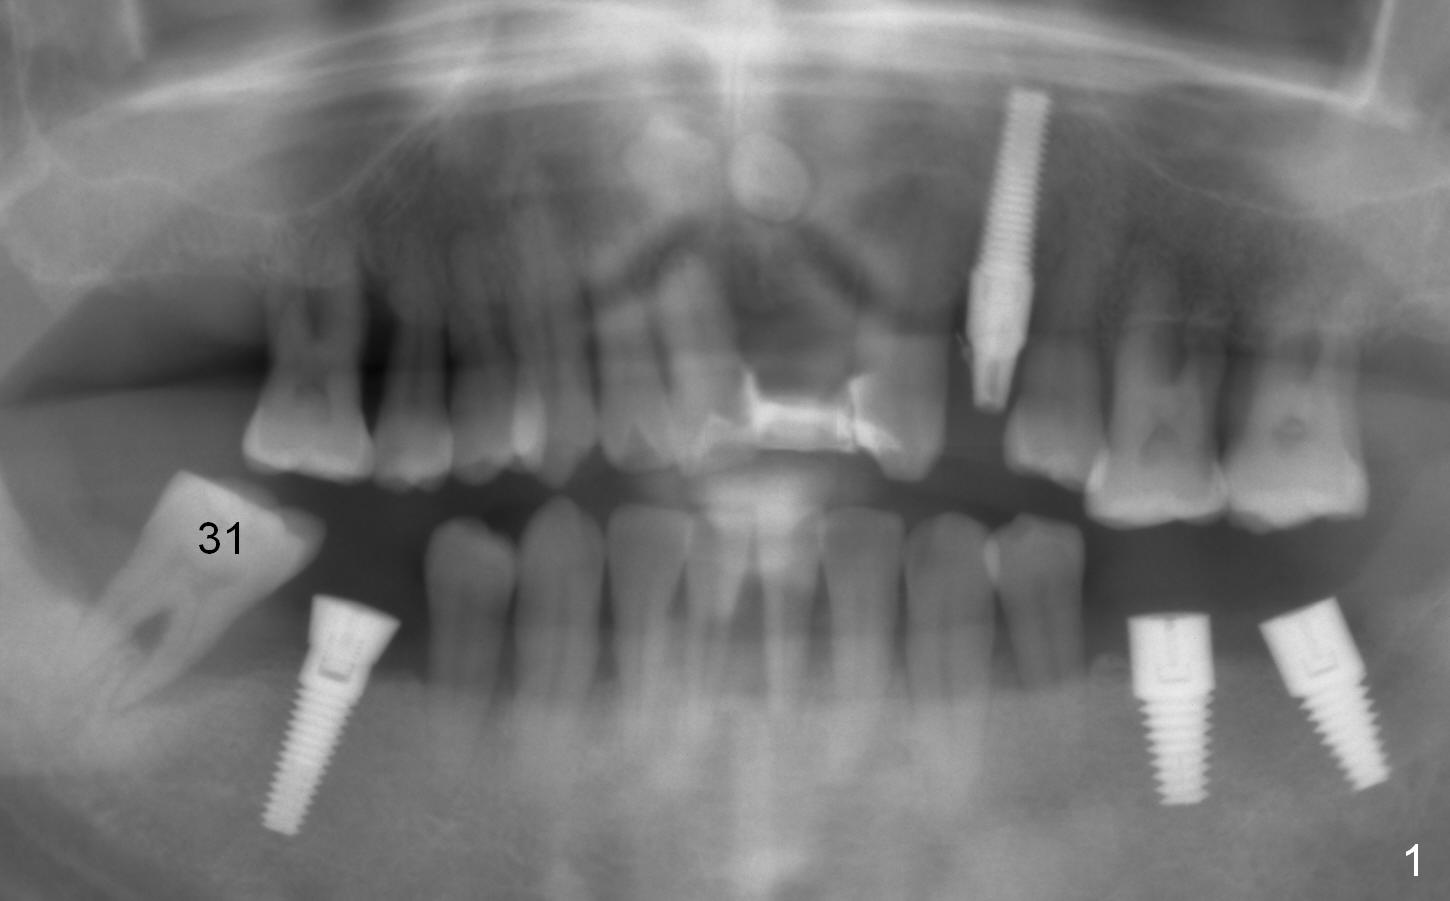

A 44-year-old man is a typical patient with chronic periodontitis (Fig.1). Periimplantitis develops following immediate implant at #31 (Fig.2). The symptom (bleeding) improves after bone graft and use of Water Pik. Now the tooth #14 appears to be non-salvageable because of gingival hemorrhage and deep pockets after previous osseous surgery. To prevent periimplantitis, an immediate implant does not need to be large or long. It has to be placed deep, and in the middle of the native bone, surrounded by bone graft. To facilitate wound healing, draw 3 tubes of blood for PRF. One of them is processed for plug in case of sinus lift. To prevent the buccal gingiva collapse, the buccal portion of the immediate provisional should extend into the socket. If the gingiva is around 4 mm, use IBS implant (Fig.3,4). Otherwise, a SM implant will be used after extraction (Clindamycin), since abutments have cuffs as long as 4.5 and 6 mm so that it is easy to place an implant as deep as possible. Initial depth will be 9 mm (bone-level), followed by Magic Drill (5.3 mm, if possible) and Magic expanders (4.3x10 and 4.8x11 mm, bone density 26-300 units).